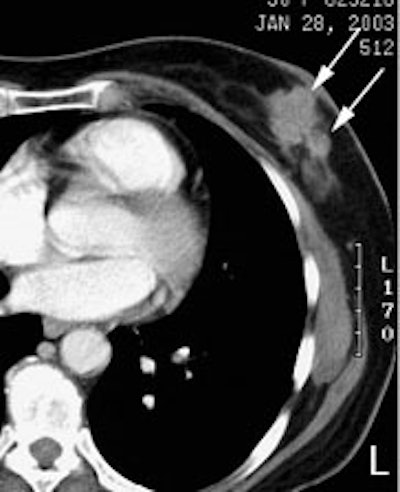

FDG PET exam for the evaluation of locoregional recurrence: The patient shown in the case below had a history of breast cancer and had developed left chest pain. She presented for the evaluation of possible metastatic disease. The CT scan revealed extensive soft tissue thickening in the left breast which was felt possibly related to scar from prior surgery and radiation therapy. There was a 2 cm lymph node in the left axilla (not shown) which was concerning for metastatic disease. Axial (center) and coronal (right) images from the patients FDG PET exam demonstrated marked increased FDG accumulation within the left breast corresponding to the soft tissue abnormality on CT. There were also multiple foci of increased uptake within the the left axilla. Biopsy revealed recurrent breast cancer. Case courtesy of CTI, The power behind PET. |

|